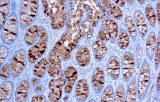

Primary antibodies for immunohistochemistry (IHC) with CE/IVD marking are essential reagents in diagnostic and research pathology, enabling the specific detection of target antigens in formalin-fixed paraffin-embedded (FFPE) tissue sections.

IHC using CE/IVD primary antibodies is a cornerstone in the characterization of gastrointestinal tumors. These antibodies assist pathologists in distinguishing epithelial from mesenchymal origins, determining tumor subtypes, and identifying primary sites in metastatic disease.

- In colorectal cancer, antibodies against cytokeratins (CK7, CK20) and transcription factors such as CDX2 facilitate accurate tumor classification and subtype differentiation.

- In gastric and esophageal adenocarcinomas, IHC highlights metaplastic and dysplastic changes, supporting early detection and prognostic evaluation.